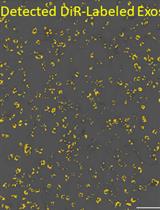

Graphical overview of extracellular vesicle (EV) isolation from plasma samples. (A) Flowchart of the isolation of extracellular vesicles from plasma, detailing plasma preparation and EV purification. (B) Transmission electron microscopy (TEM) image of EVs isolated from human plasma samples. Scale bar, 100 nm.

3. ExoView R200 platform (Software, ExoViewer 2.5.0)

5. Acquire images using a Talos L120C transmission electron microscope at an accelerating voltage of 120 kV. A TEM image of isolated EVs from human plasma is given in the Graphical overview.